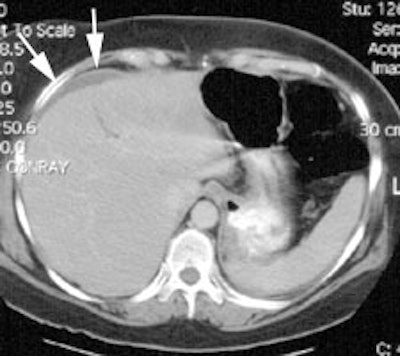

Bile Leak: The post-cholecystectomy patient shown below was being evaluated for abdominal pain and fever. The CT scan demonstrated a fluid collection anterior to the liver (white arrows- click CT image to enlarge). A hepatobiliary study demonstrated a bile leak. Increasing tracer activity can be seen over the liver corresponding to the fluid collection on the CT scan. Bile can also be seen pooling in the gallbladder fossa and extending down the right paracolic gutter. |